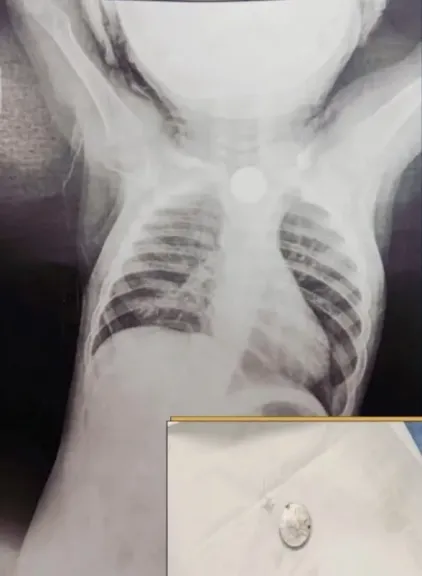

وبعد مناظرة الحالة وإجراء أشعة على الصدر، تبيّن وجود جسم غريب يُعيق مجرى الطعام والتنفس، وعلى الفور تم إدخال الطفل إلى رعاية الأطفال لاستكمال الفحوصات والعلاج اللازم، ثم نقله إلى غرفة العمليات لإجراء تدخل عاجل بالمنظار.

وتمكن الأطباء خلال العملية التي أُجريت تحت مخدر كلي، من استخراج الجسم الغريب الذي تبيّن أنه حجر بطارية لعبة أطفال صغيرة، في إجراء دقيق استغرق دقائق معدودة أنقذ حياة الطفل من مضاعفات خطيرة محتملة.